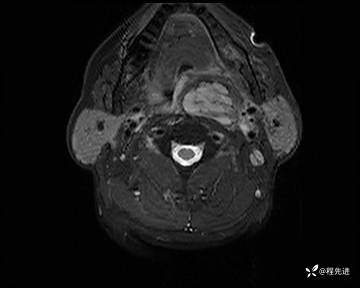

MRI平扫+增强:

T2压脂: